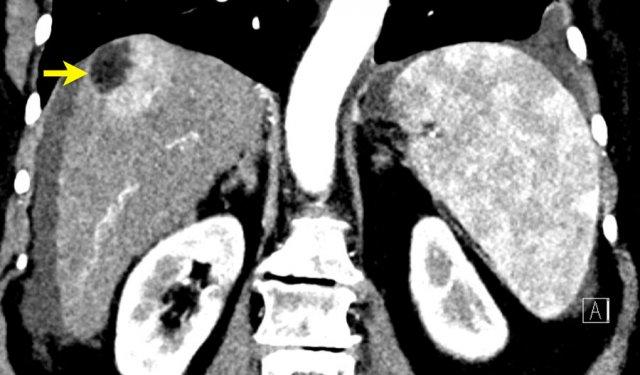

LI-RADS 4 – Có thể là HCC

Trong tổng số các tổn thương LR-4, khoảng 74% là HCC và 81% là ác tính (1).

Việc phân loại một tổn thương là LR-4 phụ thuộc vào kích thước tổn thương, sự hiện diện của APHE và số lượng đặc điểm chính bổ sung (xem bảng LIRADS).

Đây là một tổn thương rất nhỏ, kích thước dưới 10 mm, với tăng ngấm thuốc động mạch không dạng viền (nonrim APHE) và một đặc điểm bổ sung, tức là LI-RADS 4.